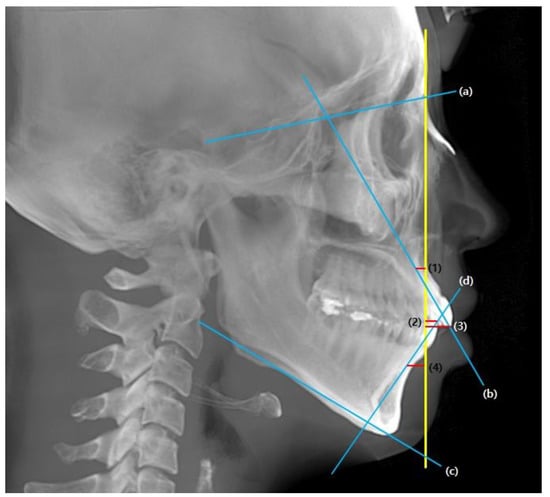

For the pre-treatment (T0) and post-treatment (T1) CBCT images, a coordinate system with the Frankfort horizontal plane parallel to the xy-plane, the line connecting the orbitale parallel to the x-axis, and the pogonion being set as the zero point was followed. CBCT cephalograms were synthesized from the reoriented CBCT data, and linear measurements were performed using the OnDemand3D software (Cybermed, Seoul, Korea) (Figure 1). To determine the total distance of the incisor movement, a vertical reference line (vert T) constructed through a stable craniofacial structure was used to measure the distance between the incisal tip and root apex between T0 and T1 (Figure 2).

Figure 2. Cephalometric reference planes and measurements. Yellow, vertical reference line (vert T); Blue, (a) S-N (b) U1-SN (c) mandibular plane (d) IMPA; Red, (1) U1 apex (2) L1 tip (3) U1 tip (4) L1 apex. Incisal movements were quantified by measuring the horizontal distance from incisor tip and apex to vert T, which is Nasion perpendicular line.